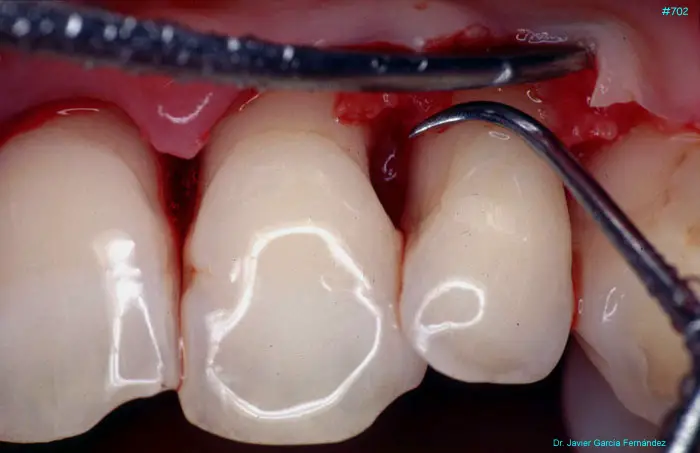

Atlas of Surgical Techniques in Periodontics. Chapter III. Atlas de Técnicas Quirúrgicas en Periodoncia